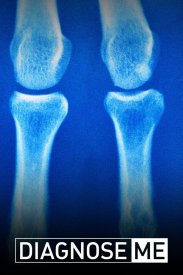

Поставьте мне диагноз

2015 реальное ТВ

Вы увидите, как врачи становятся настоящими детективами, решая удивительные и странные случаи, которые не поддаются ни одному из одарённых специалистов. Невероятные повороты событий, когда врачам прих...